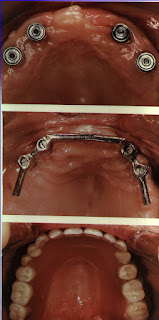

La cirugía convencional de implantes, es una cirugía ambulatoria, indolora y con mínima repercusión para el paciente. Muchos de los pacientes al día siguiente realizan una vida completamente normal.

La inflamación que se produce es mínima, precisando un tratamiento analgésico por un corto periodo de tiempo.Pasada la primera semana, el paciente no notará ninguna molestia ni sensación extraña, exactamente igual que antes de realizar el tratamiento. Y por implante el cirujano se tarda unos 30 minutos...